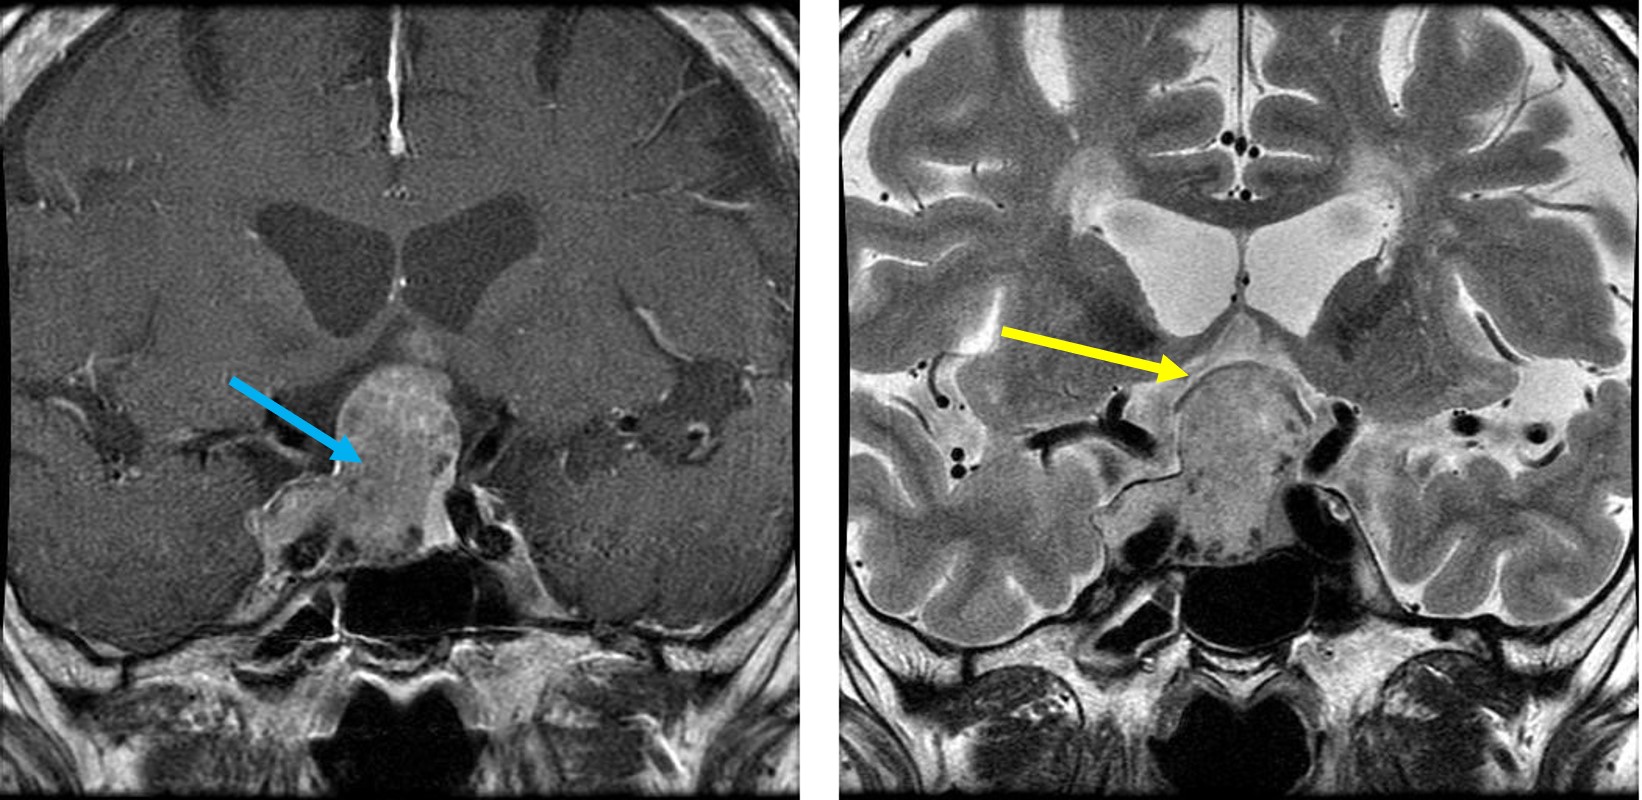

下垂体腺腫のMRI 青矢印:下垂体腺腫、黄色矢印:圧迫されている視神経